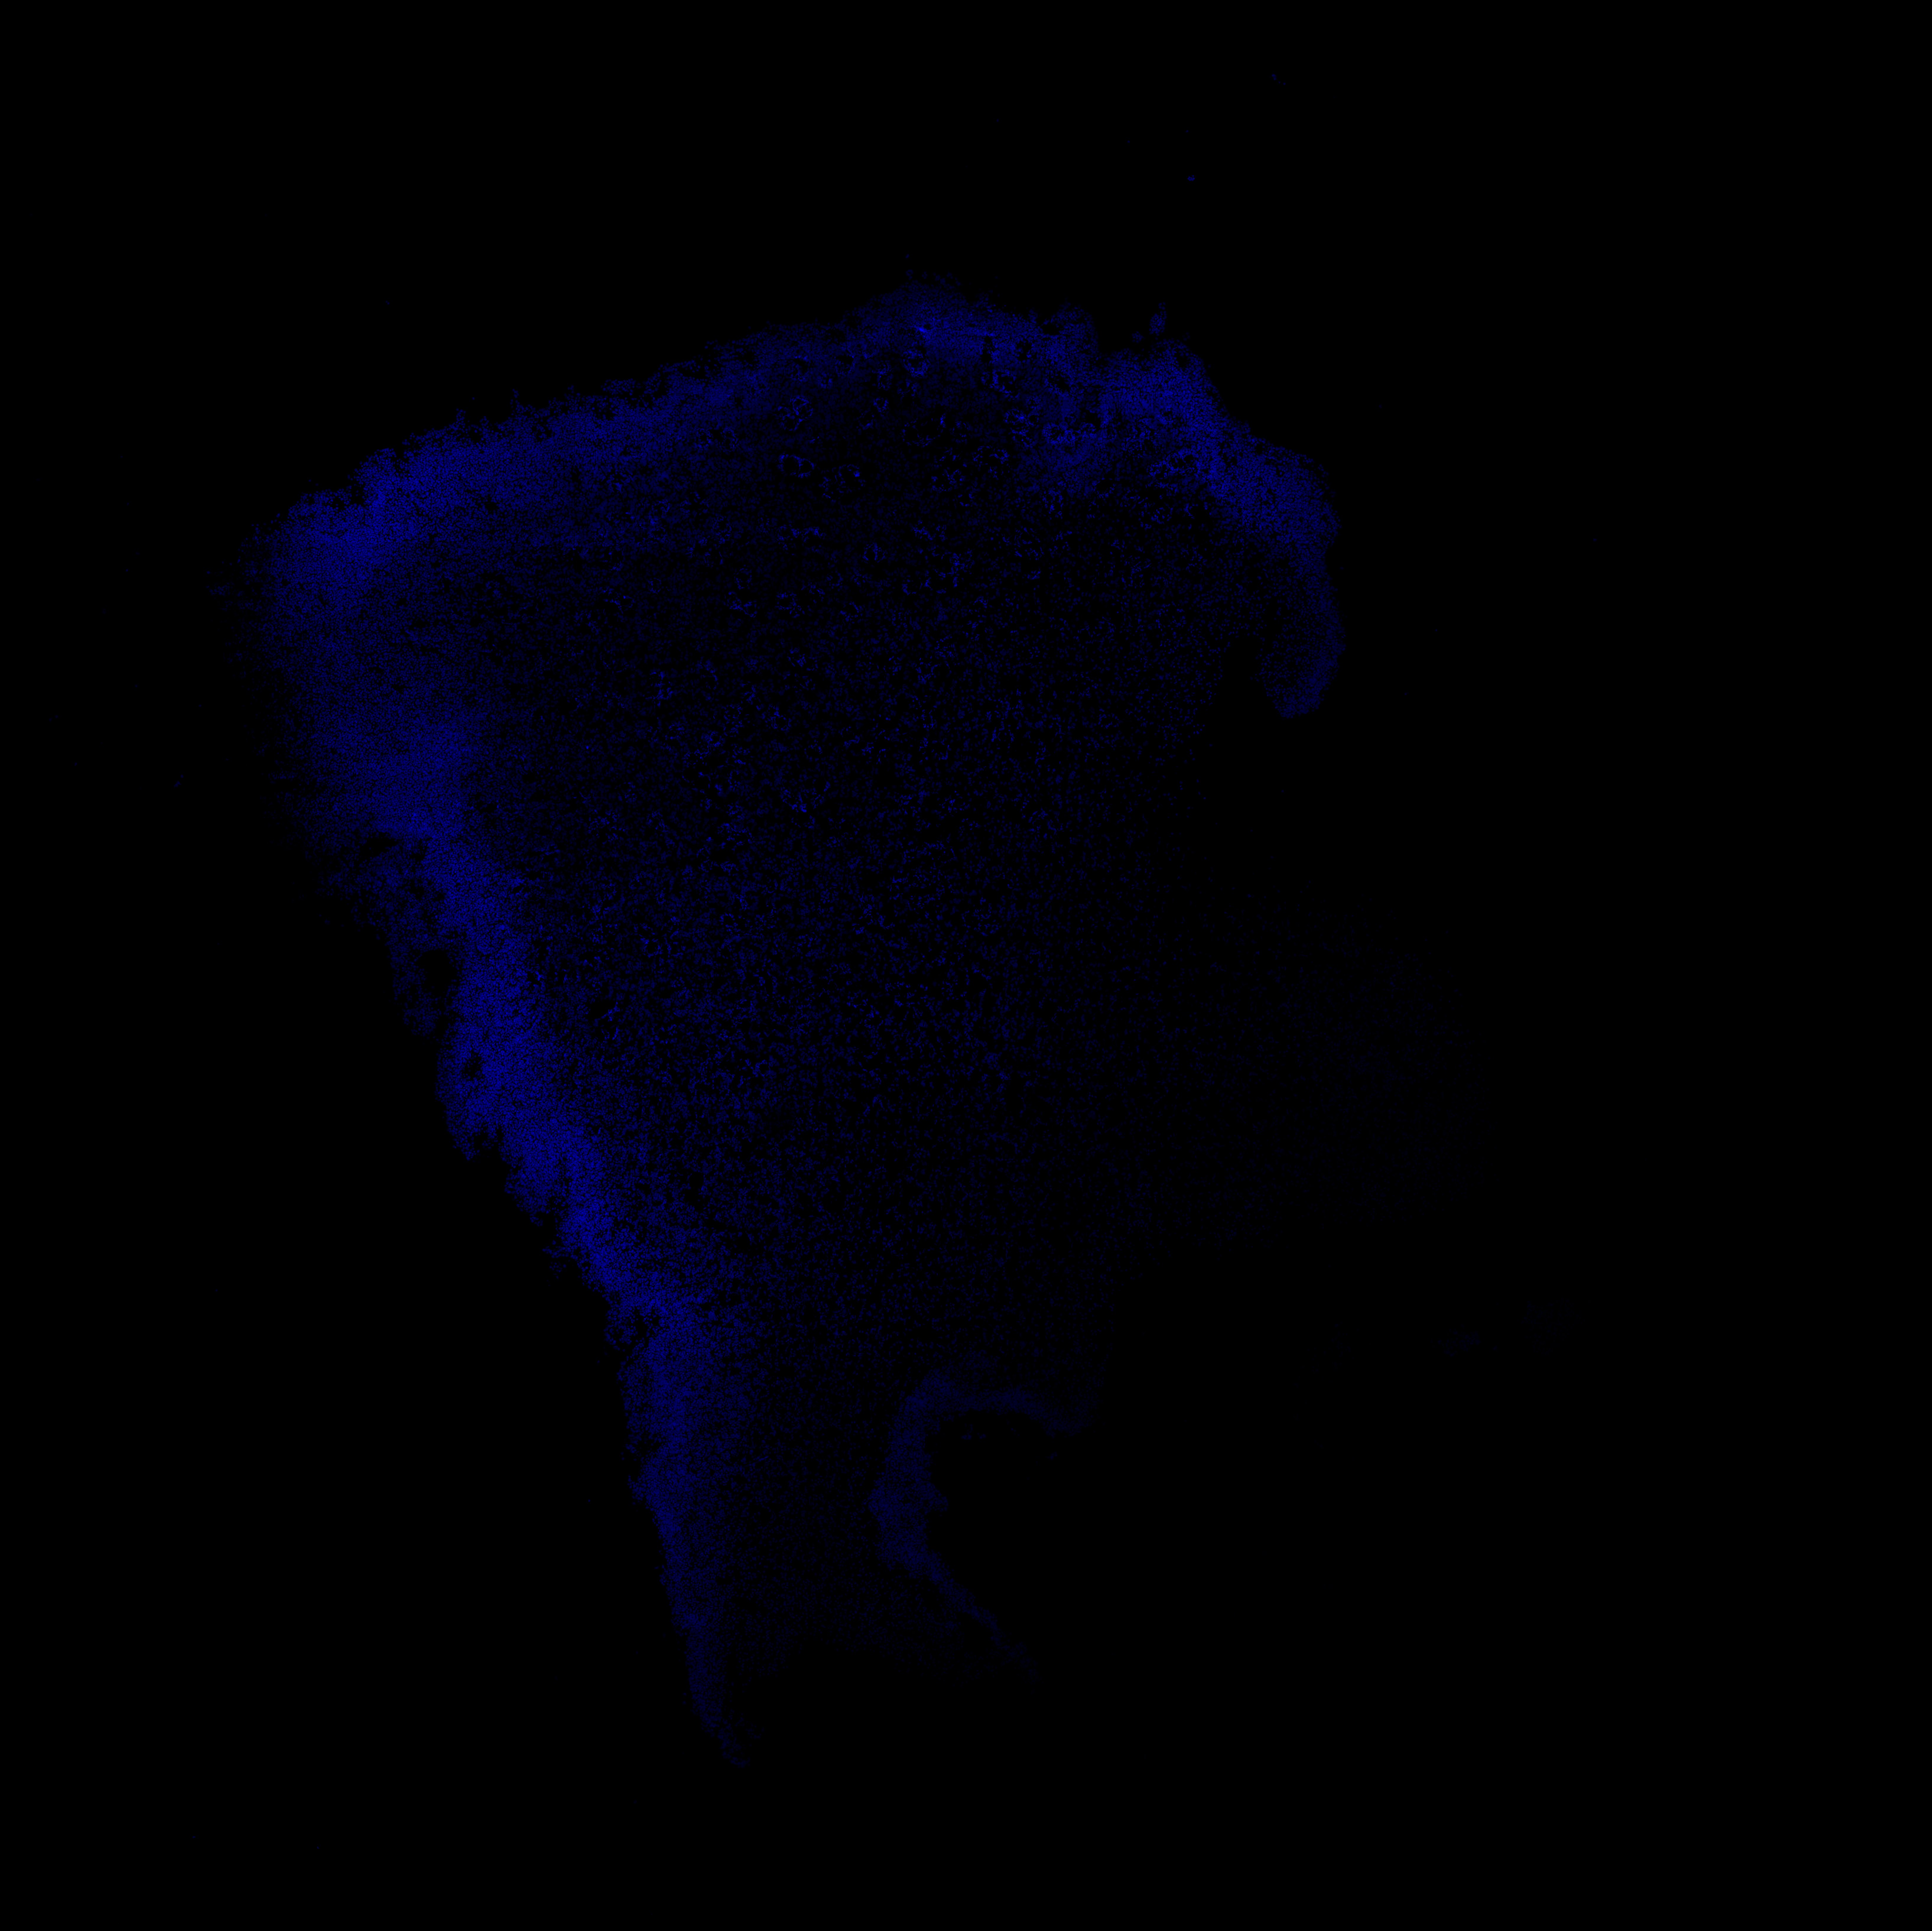

An anatomical analysis of the developing human midbrain from 6 post-conceptional weeks (PCW) to 22 PCW reveals increased tissue complexity, characterized by the emergence of dopaminergic nuclei, as highlighted by immunofluorescence analysis for tyrosine hydroxylase (TH).

DAPI

6PCW human midbrain